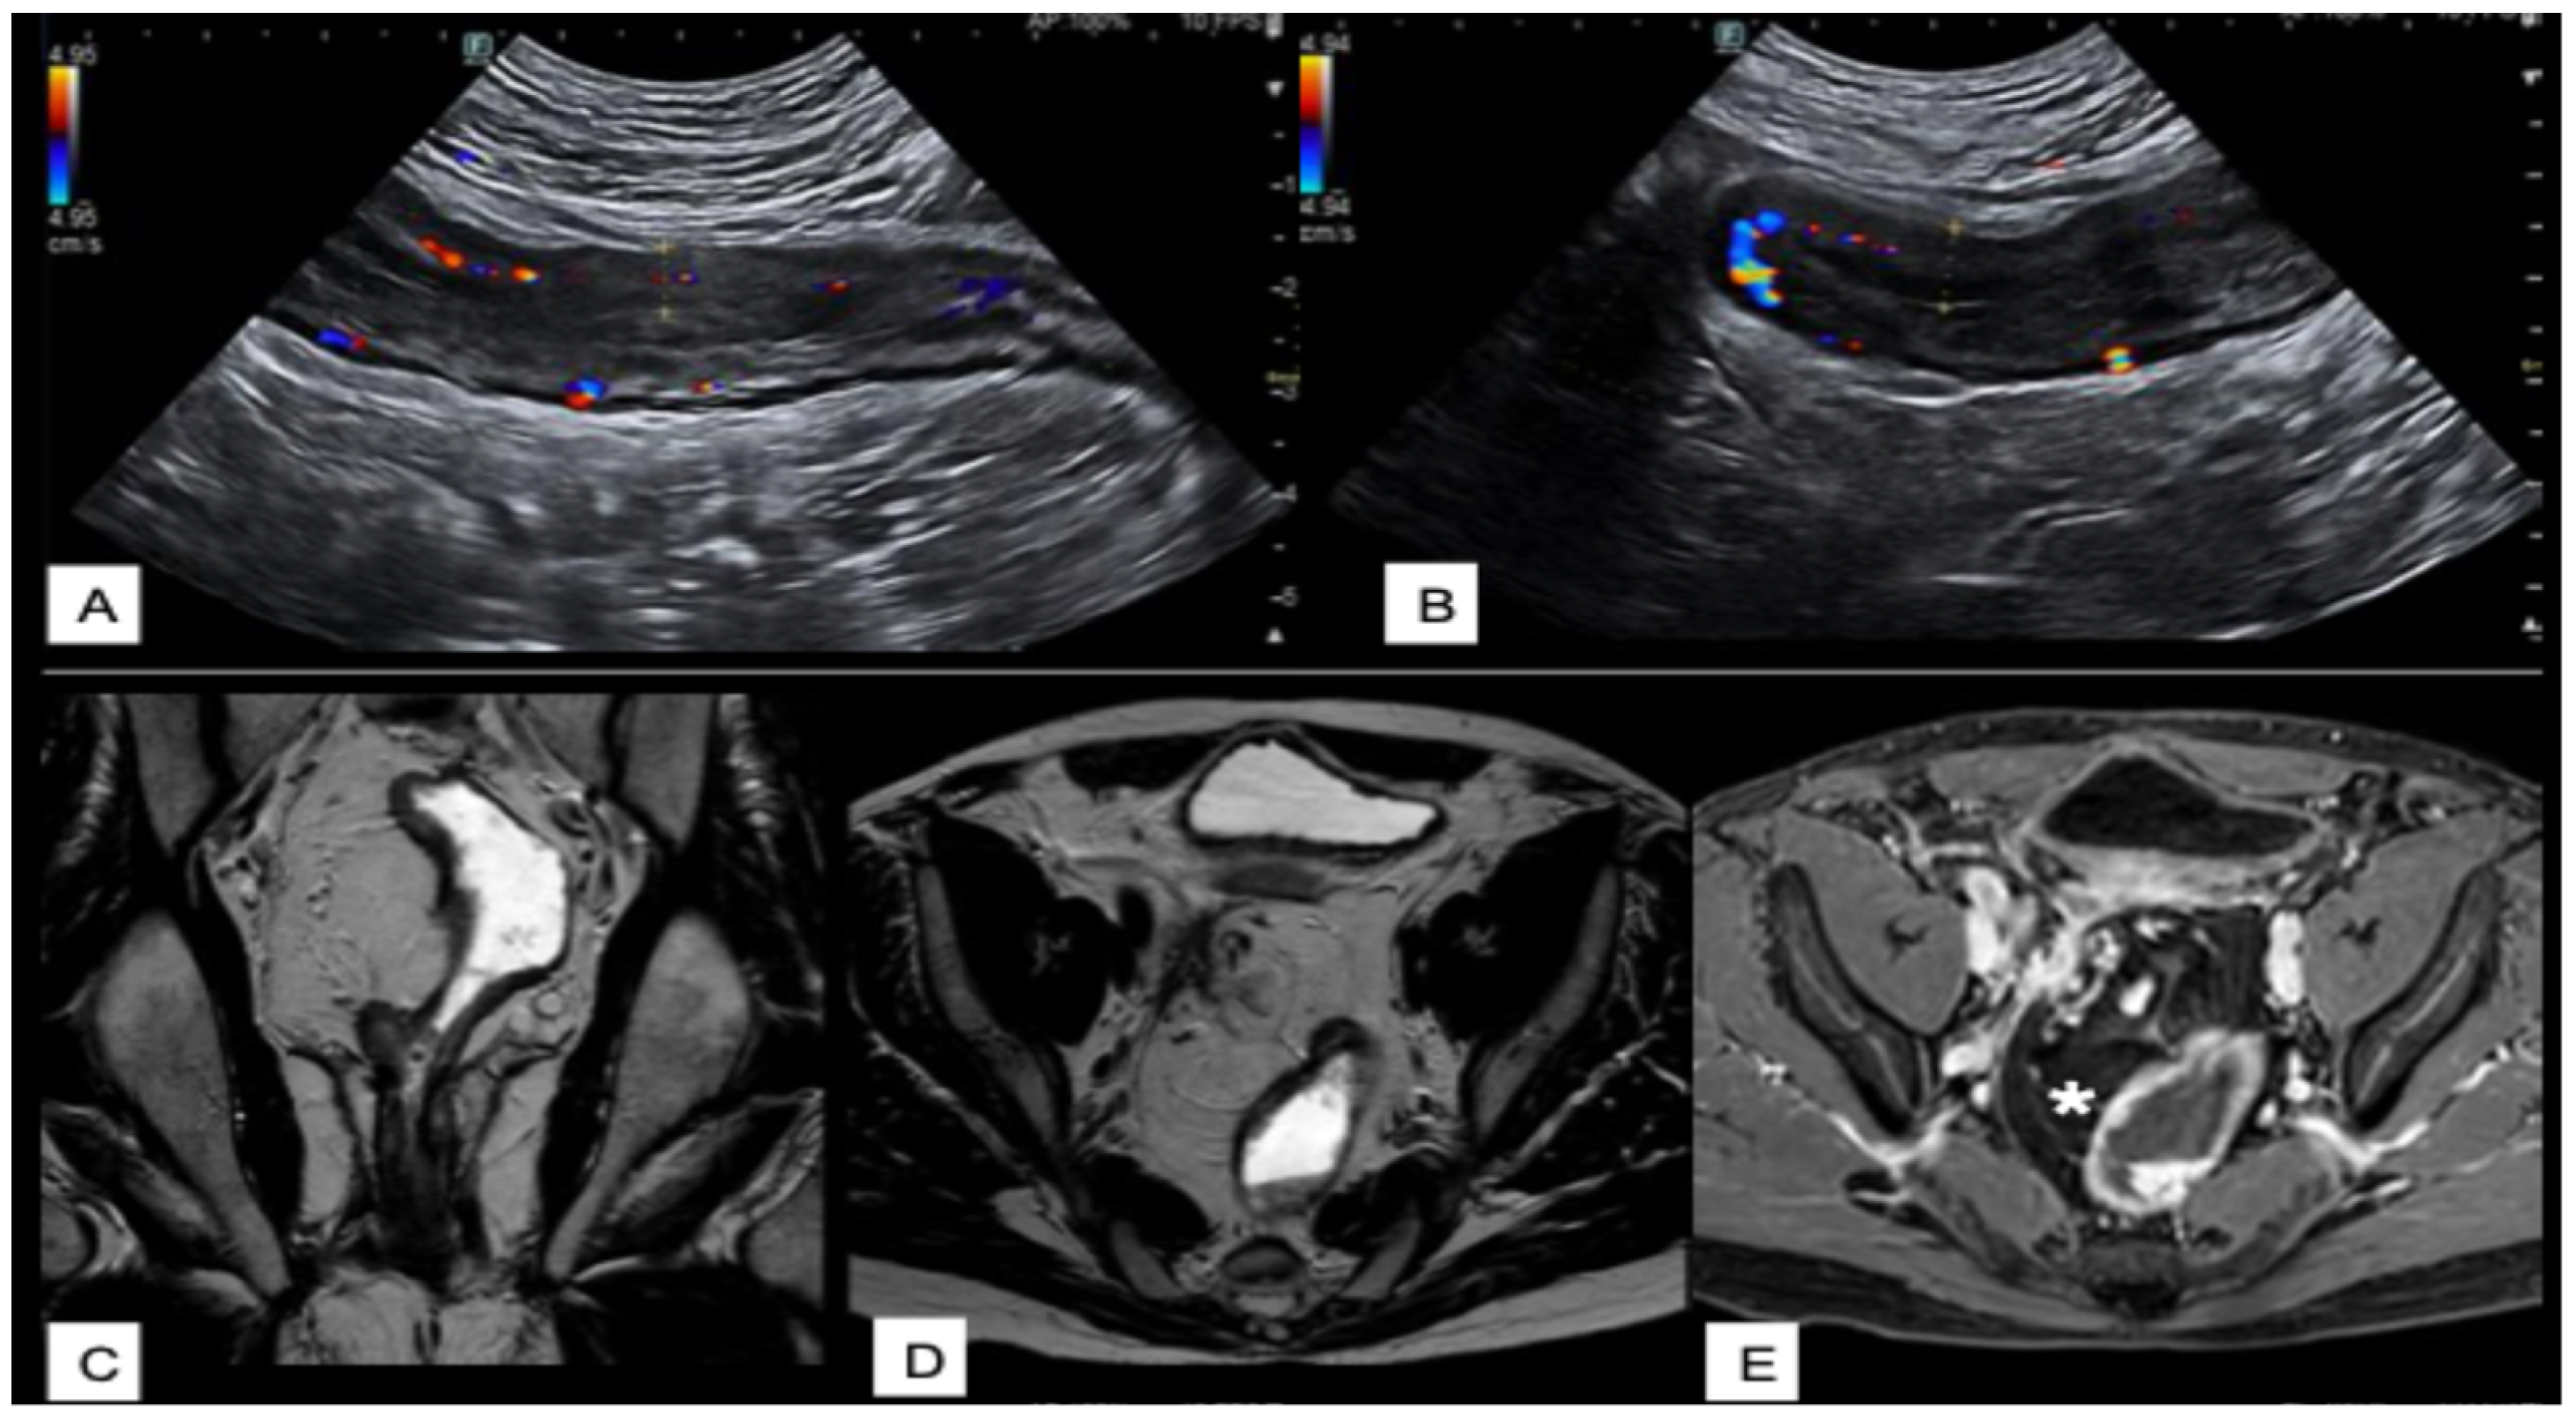

Intestinal Ultrasounds Imaging Findings and Scoring Systems

- Gallego, J.C.; Echarri, A. Role of magnetic resonance imaging in the management of perianal Crohn’s disease. Insights Imaging 2018, 9, 47–58. [Google Scholar] [CrossRef]

- Gage, K.L.; Deshmukh, S.; Macura, K.J.; Kamel, I.R.; Zaheer, A. MRI of perianal fistulas: Bridging the radiological-surgical divide. Abdom. Imaging 2013, 38, 1033–1042. [Google Scholar] [CrossRef]

- Celikyay, F.; Yuksekkaya, R.; Yuksekkaya, M.; Kefeli, A. Color Doppler Ultrasound Assessment of Clinical Activity in Inflammatory Bowel Disease. Curr. Med. Imaging 2021, 17, 741–750. [Google Scholar] [CrossRef]

- Ripollés, T.; Martínez-Pérez, M.J.; Blanc, E.; Delgado, F.; Vizuete, J.; Paredes, J.M.; Vilar, J. Contrast-enhanced ultrasound (CEUS) in Crohn’s disease: Technique, image interpretation and clinical applications. Insights Imaging 2011, 2, 639–652. [Google Scholar] [CrossRef]